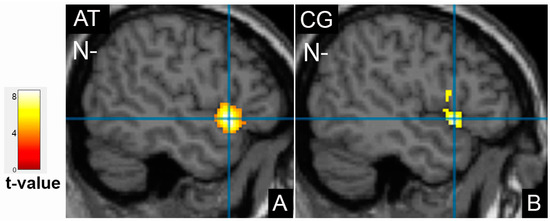

3.3. Comparison of Brain Activation Patterns in Patients before Treatment and Healthy Controls

| Cluster Location | Emotion | Extent | t-Value | p (FWE Corrected) | MNI Coordinates |

|---|---|---|---|---|---|

| Control group, cortical activation | |||||

| Frontal cortex | |||||

| Right middle frontal gyrus | N | 2228 | 8.91 | <0.001 | 54;14;34 |

| Right inferior frontal gyrus, precentral gyrus | N- | 946 | 6.05 | <0.001 | 42;6;30 |

| Right inferior frontal gyrus | P+ | 280 | 7.29 | 0.041 | 46;36;8 |

| Left inferior frontal gyrus, insula | P+ | 358 | 5.93 | 0.014 | −36;24;4 |

| Limbic lobe | |||||

| Left amygdala | N | 298 | 8.29 | 0.009 | −28;0;−24 |

| Occipital cortex | |||||

| Left middle occipital gyrus | N | 2977 | 9.13 | <0.001 | −40;−78;0 |

| Right fusiform gyrus, BA37 | P+ | 3809 | 12.41 | <0.001 | 36;−72;−20 |

| Temporal cortex | |||||

| Left superior temporal gyrus, BA22 | N- | 1689 | 8.4 | <0.001 | −50;14;−6 |